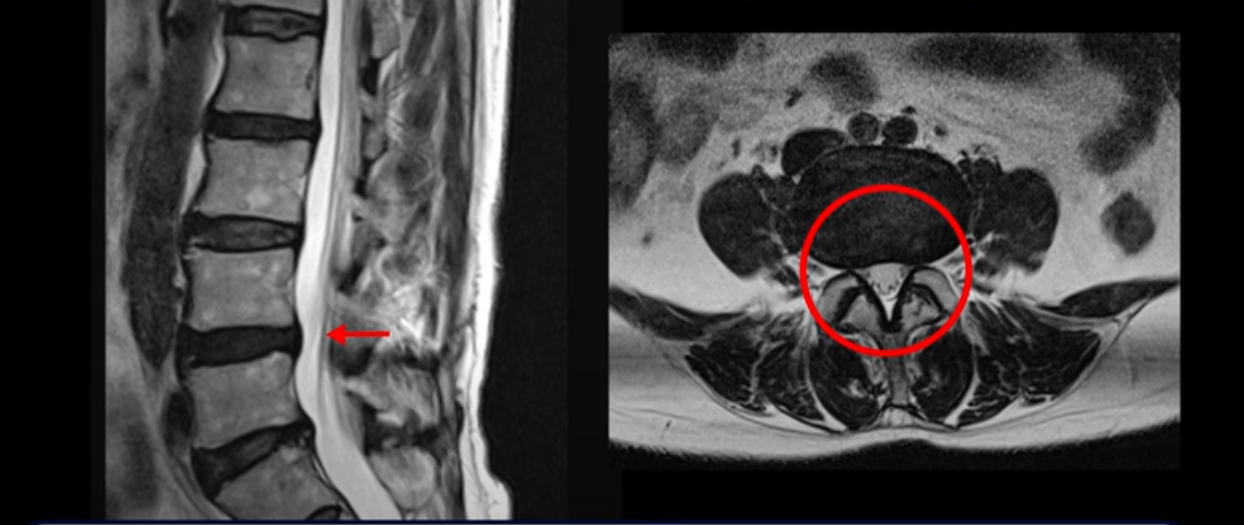

척추관이 가장 좁아진 4번 5번을 보면 중심성 협착이 있지만 많이 심하지는 않습니다

그런데 저희가 협착증 발병과 치료에 근육이 너무나도 중요하다고 하는 이유는 이렇게 신경 구멍이 심하게 좁아지지 않은 환자도 근육 상태가 안 좋아지면 얼마든지 신경학적 방사통이 생길 수 있기 때문입니다. 이분은 몇 개월 전 아기를 보면서 허리를 무리하게 쓴 후 다리 증상이 시작되었고 그 뒤에 해외 여행 다녀온 이후 증상이 급격히 악화됩니다. 60세 이후 노화와 퇴행으로 신경 구멍들이 조금씩 좁아지고 근육은 줄어들고 약해진 상태에서 무리한 일이나 운동으로 근육의 문제가 심해지면 근육이 허리를 잘 지탱하지 못하니까 신경 눌림 증상이 얼마든지 발생할 수 있습니다. 그런데 심해 보이지 않는 협착도 이 환자분처럼 일단 방사통이 생기고 신경주사가 듣지 않으면 수술하자는 얘기를 듣게 됩니다.

저희가 계속 반복해서 얘기하지만 협착증 증상이 생기고 악화되는 이유는 신경 구멍이 노화로 좁아져서만 그런 게 아닙니다. 나이가 들면서 반드시 근육도 동시에 나빠지기 때문에 협착증이 생기는 겁니다. 신경 구멍이 좁아져 있는 상태에서 근육은 줄어들고 망가지면서 허리를 잘 지지하지 못하니까 신경이 눌리는 것입니다. 그러니까 협착증이 주로 60세 이후 나이든 사람들한테 생기는 것입니다. 그런데도 아직도 많은 분들이 근육의 중요성을 모르고 신경 치료만 하고 있습니다. 하지만 근육과 신경은 떼놓고 생각할 수가 없습니다. 근육이 나빠지면 신경 눌림이 심해져서 협착증 증상이 더 악화되고 또 신경이 많이 눌릴수록 근육도 더 빨리 나빠집니다. 반대로 근육이 좋아지면 신경 눌림이 줄어들고 협착증이 좋아집니다.